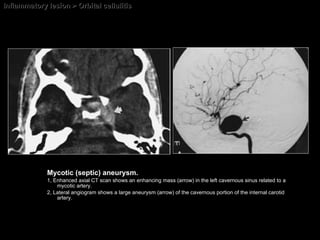

Inflammatory lesion > Orbital cellulitis Mycotic (septic) aneurysm.  1, Enhanced axial CT scan shows an enhancing mass (arrow) in the left cavernous sinus related to a mycotic artery.  2, Lateral angiogram shows a large aneurysm (arrow) of the cavernous portion of the internal carotid artery.